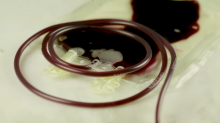

¿En nuestro cuerpo fluye sangre o dinero?

Donar sangre es considerado un acto de generosidad y solidaridad con la sociedad, pues algunos necesitan del preciado líquido para seguir viviendo. Sin embargo...